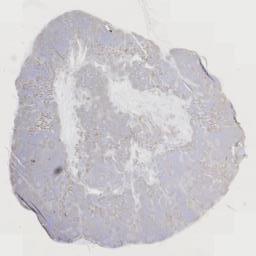

大体所见: 灰白组织2枚,直径1.8-2.5cm,切面灰白。

免疫组化: 免疫组化:Ki-67(+),CD1O(+),CD20(+),Pax-5(+),CD3(+),CD5(+)。CD23(FDC网),Bcl-2(+),Bcl-6(+),MUM1(+),CD21(FDC网),CyclinD1(-),CD43(+),S-100(+),CD68(+).